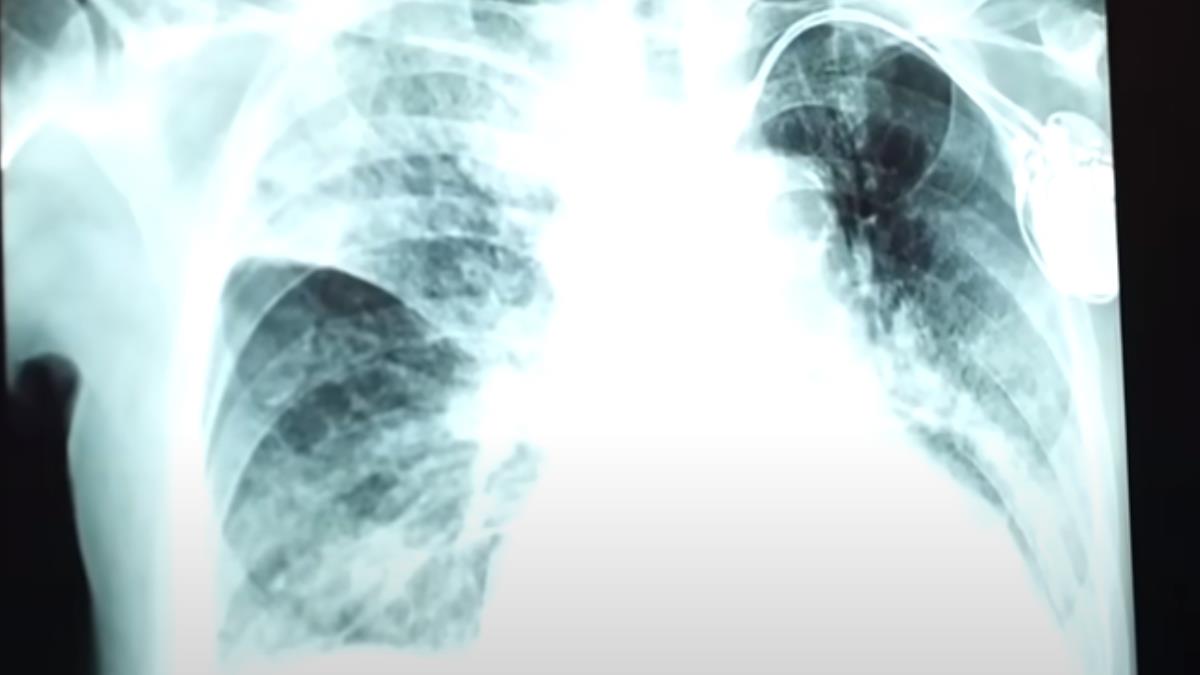

比較正常的肺都會有這種像樹枝狀的地方,這是血管,不正常就像這種網狀就是纖維化。這名患者,因為染上嚴重肺炎,從氣喘久咳,最終導致纖維化,已經是永久性傷害,再也回不去了。

台安醫院家醫科醫師:「當初的發炎很嚴重,纖維化機率比較高,慢慢可以復原,但不見得可以復原到最初。」

肺臟從原應柔軟如海綿的狀態變得像菜瓜布一樣粗糙,俗稱「菜瓜布肺」,一但急性發作會白成一片,這時候的存活率只剩0.9年,比癌症還可怕。冬季是病毒的溫床,新冠肺炎正悄悄捲土重來,2023年3到12月新冠肺炎已經累積388例死亡,有348人是65歲以上年長者,當中不少就是死於肺纖維化,而下一波大流行的新冠變異株JN.1恐怕在春節前夕造成大流行,醫界預估確診者和死亡率都將增加。

聯合醫院中興院區內科醫師姜冠宇:「像是新冠像是流感,因為引起嚴重免疫反應導致整個肺都白掉,肺泡就會跟沼澤一樣,沼澤裡養的就是肺炎鏈球菌,所以為何打流感疫苗還要一起打鏈球菌,就是這個道理。」